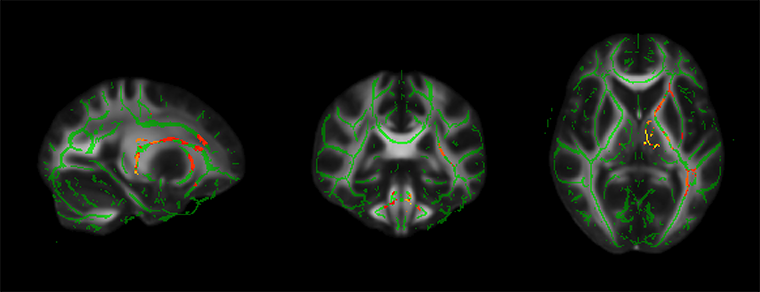

研究團隊發現,細懸浮微粒與二氧化氮濃度減少與老年人的注意力提升呈正相關。更重要的是,磁振造影顯示這些污染物濃度下降,與多個掌管注意力與記憶力的大腦白質區域結構完整性有密切相關。

▲PM2.5降低幅度越大與大腦顯著相關的區域,紅黃色為統計顯著區域。(圖/國立陽明交通大學提供)